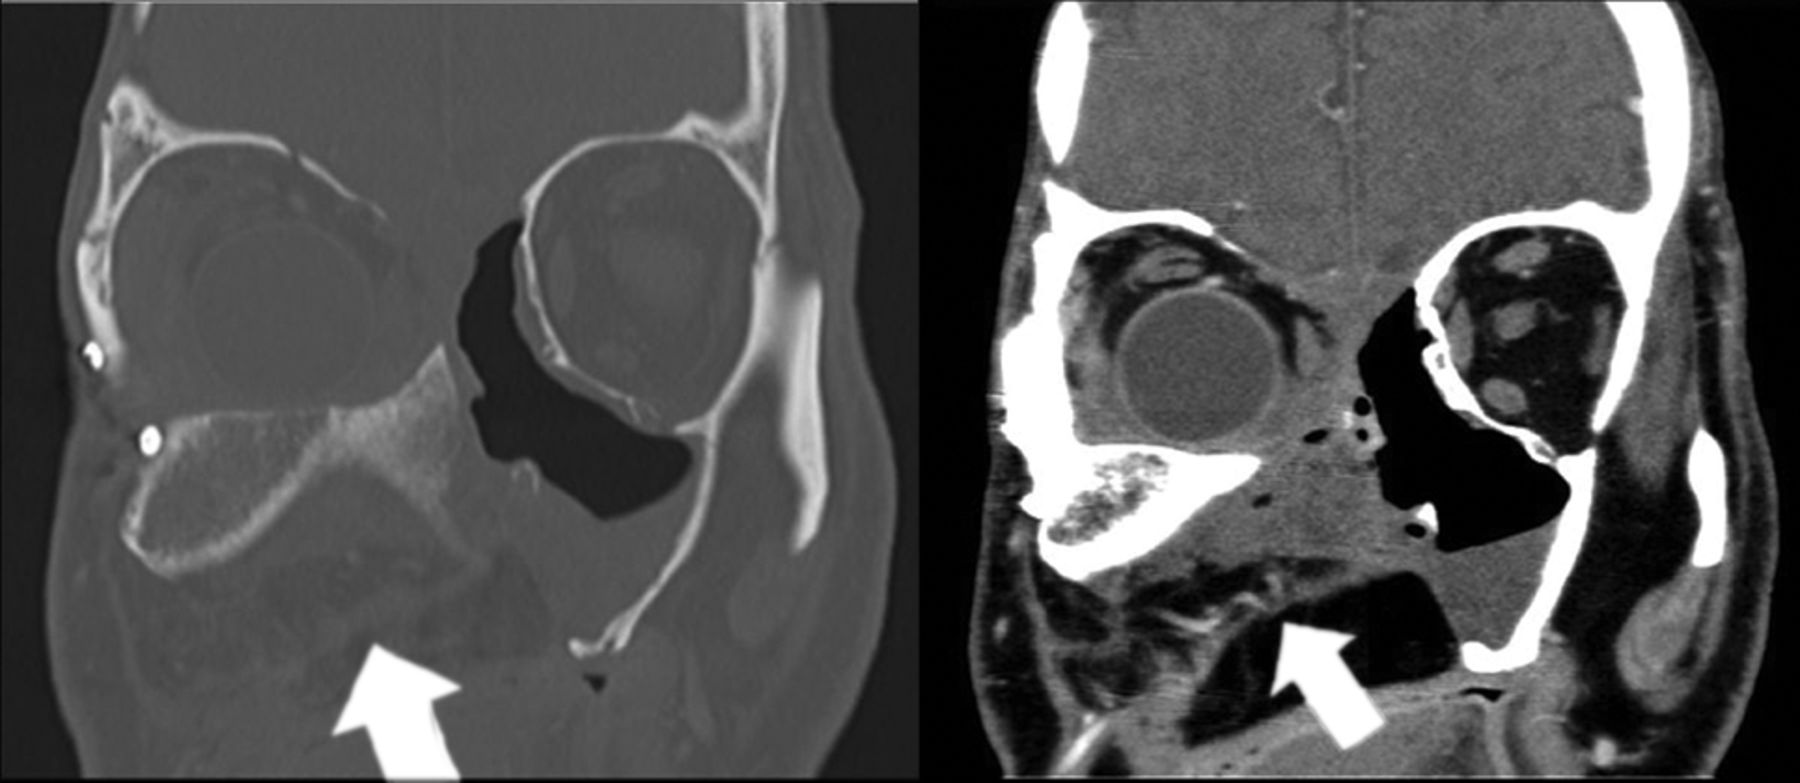

The internal oblique muscle from the flap eliminates the maxillectomy cavity, thereby preventing the presence of dead space (arrows).

A, An iliac crest–internal oblique flap has been harvested based on the DCIA and DCIV (asterisk). B, The iliac crest is shown inset into a palatomaxillectomy defect with the crest oriented toward the bottom (arrow). The internal oblique muscle based on the ascending branch of the DCIA has been brought through the palatal defect, medial to the iliac bone (curved arrow). This patient underwent an orbital exenteration, and the internal oblique muscle (IOM) is shown filling the orbital defect as well as obliterating the maxillectomy cavity. Rigid fixation (RF) is achieved to the lateral and superior orbital rim. The upgoing arrow shows a dental implant placed into the neoalveolar ridge. C, The internal oblique muscle, which is not optimally visualized on bone window, is used to fill the maxillectomy defect (arrow).